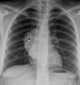

Chest mass

A chest radiograph, called a chest X-ray (CXR), or chest film, is a projection radiograph of the chest used to diagnose conditions affecting the chest, its contents, and nearby structures. Chest radiographs are the most common film taken in medicine. [Source: Wikipedia ]